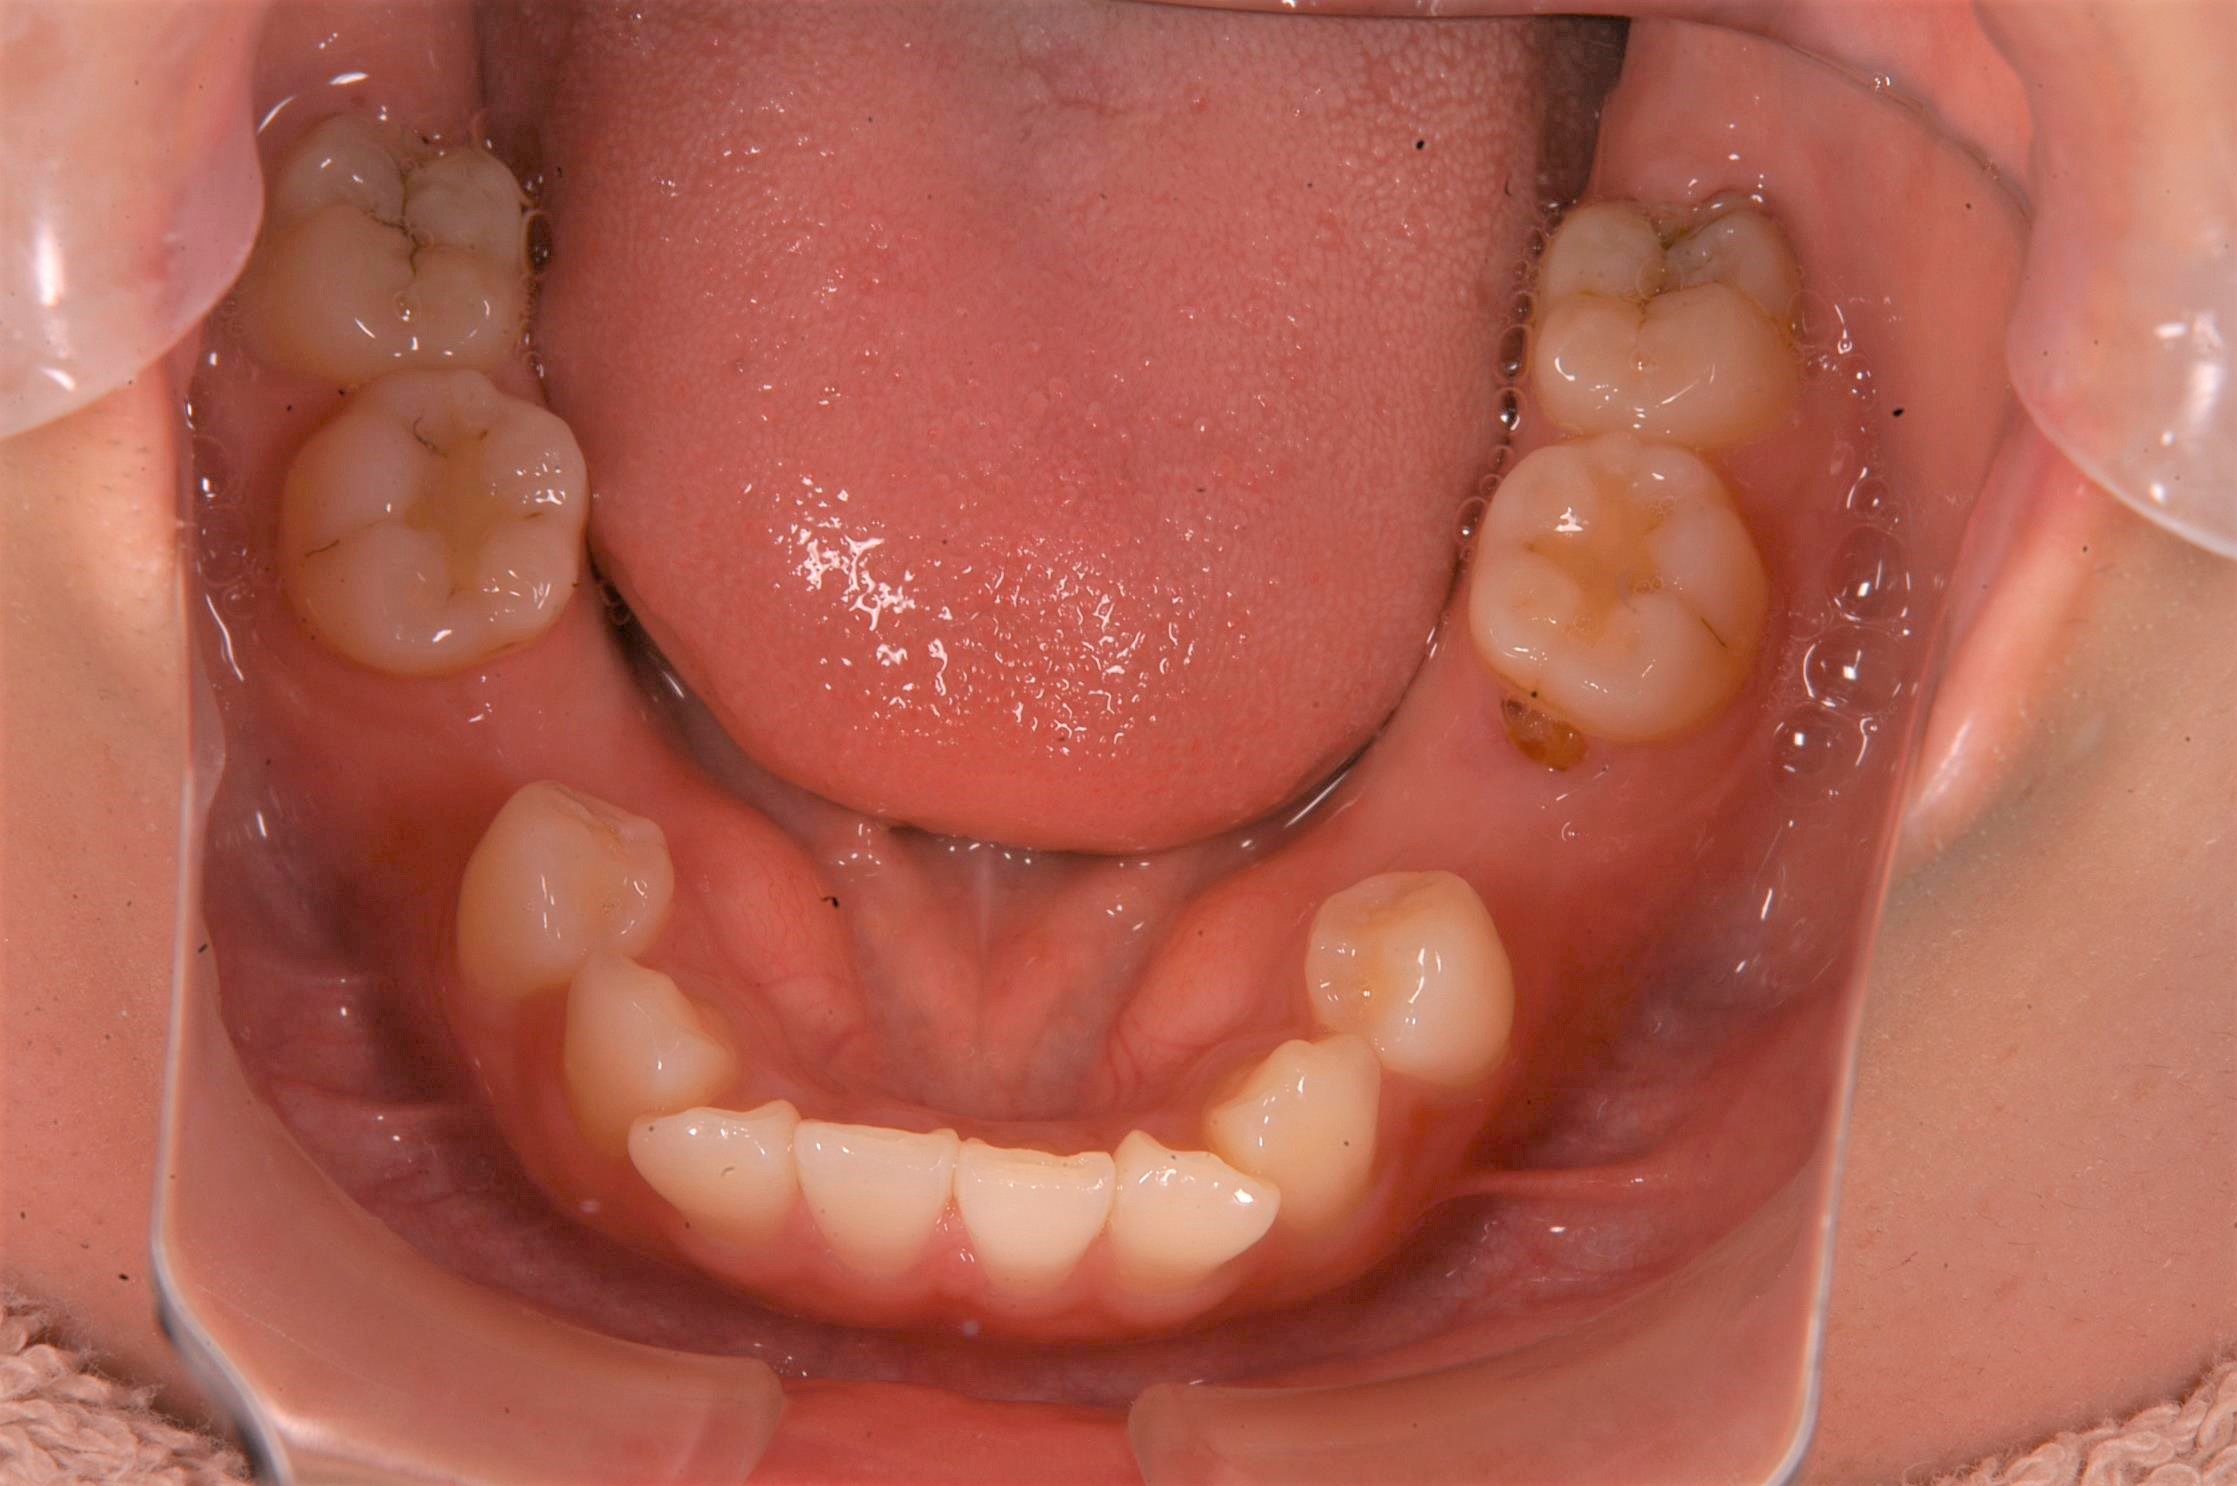

治療後

| 治療内容 | インプラント | 期間 | 4ヶ月 |

|---|---|---|---|

| 治療回数 | 10回 | 費用 | 880,000円(税込) |

| リスク 副作用 |

喫煙者・歯周病の方はインプラント生存率が著しく低下します | ||